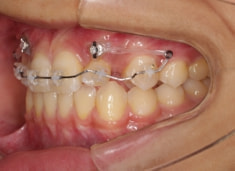

治療前

治療開始時